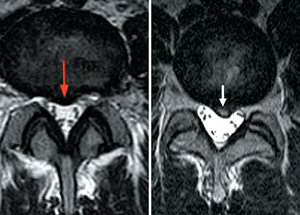

Which patient has lower back pain? The MRI image is sensitive, but may not correlate with clinical symptoms. (See correct answer at end of article.)

Which patient has lower back pain? The MRI image is sensitive, but may not correlate with clinical symptoms. (See correct answer at end of article.)

Answer: image on the left (red arrow).